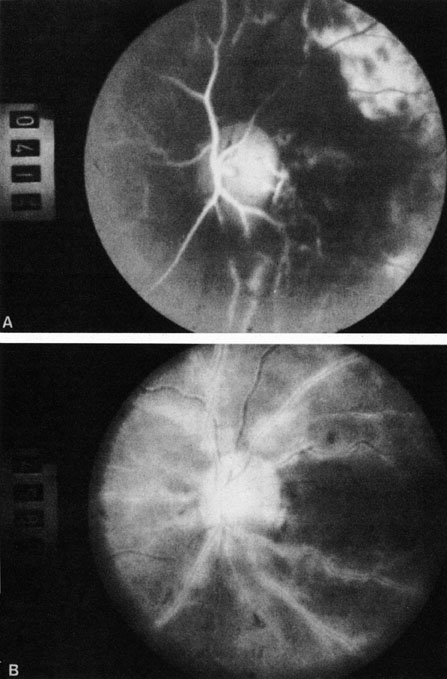

Ophthalmic artery obstruction is characterized by an initial opacification of the entire retina in a manner similar to that of central retinal artery obstruction (Fig. 4A). The cherry-red spot may or may not be present, however.119 The difference between an ophthalmic artery obstruction and central retinal artery obstruction is that in an ophthalmic artery obstruction, with time, optic atrophy develops, as does varying amounts of pigmentation due to the lack of perfusion of the retinal pigment epithelium (see Fig. 4D). This pigment is generally diffusely scattered throughout the posterior pole but it may also be seen in greater amounts in the periphery.

Fig. 4. A: Ophthalmic artery obstruction showing a cherry-red spot: the visual acuity was no light perception. B: At 26.2 seconds, the retinal vessels are filled, but no dye is seen in the choroidal circulation. C: By 37.7 seconds, the choroidal circulation is more visible, and a doughnut-shaped area of hypofluorescence is noted. D: Six months after the initial photographs, optic atrophy is present, as is atrophy of the retinal vessels. Diffuse pigment disturbance is evident.

Intravenous fluorescein angiography generally shows moderate to marked abnormalities in the filling of the choroid, in addition to a delay in filling or even nonfilling of retinal vessels (see Fig. 4B and 4C). Staining of the retinal pigment epithelium can also be seen; this staining either can occur locally in the macular area or it can be diffuse.119 The electroretinogram shows abnormalities of both a- and b-waves, reflecting ischemia to both the inner and outer retina. Almost all reported patients have had an initial visual acuity of no light perception; virtually no patients can be expected to have a final visual acuity better than that.119 An acuity of no light perception is a clue to the presence of an ophthalmic artery obstruction. Because relatively few patients with central retinal artery obstruction have an initial visual acuity of no light perception, no light perception usually suggests the likelihood of some obstruction of the choroidal circulation.14